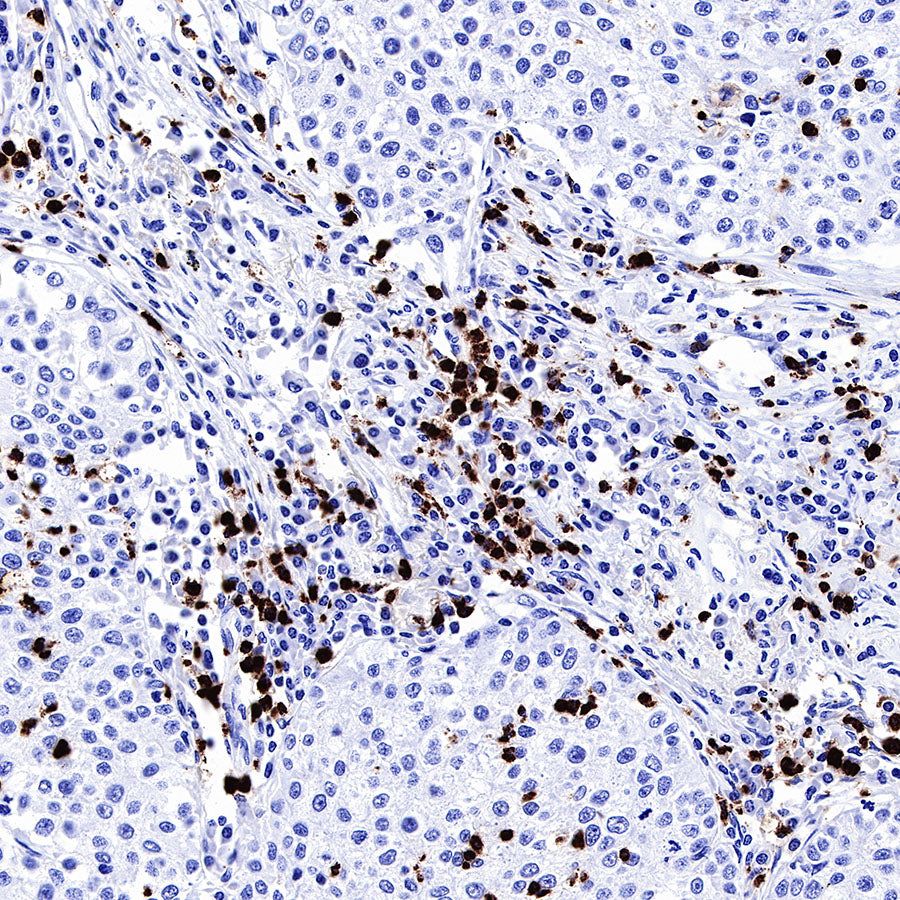

IHC shows positive staining in paraffin-embedded human lung squamous cell carcinoma. Anti-MPO antibody was used at 1/1000 dilution, followed by a HRP Polymer for Mouse & Rabbit IgG (ready to use). Counterstained with hematoxylin. Heat mediated antigen retrieval with Tris/EDTA buffer pH9.0 was performed before commencing with IHC staining protocol.

IHC shows positive staining in paraffin-embedded human gastric cancer. Anti-MPO antibody was used at 1/1000 dilution, followed by a HRP Polymer for Mouse & Rabbit IgG (ready to use). Counterstained with hematoxylin. Heat mediated antigen retrieval with Tris/EDTA buffer pH9.0 was performed before commencing with IHC staining protocol.